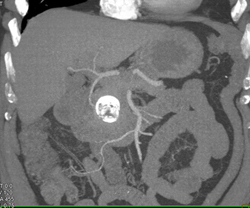

Occlusion of Splenic Vein By Pancreatic Cancer